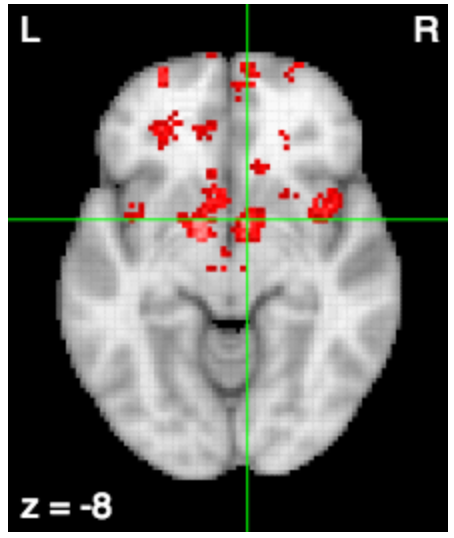

Friston et al. (1994) Human Brain Mapping

food, weight, obese, eating, foods, obesity, reward, energy, hunger, calorie, intake, bmi, mass, body, satiety, normal, cues, responsivity, women, overweight, appetite, individuals, caloric, increases, lean, index, fat, pictures, gain, hungry, images, bed, palatable, craving, receipt, water, overeating, meal, kg, motivation

neurosynth.org